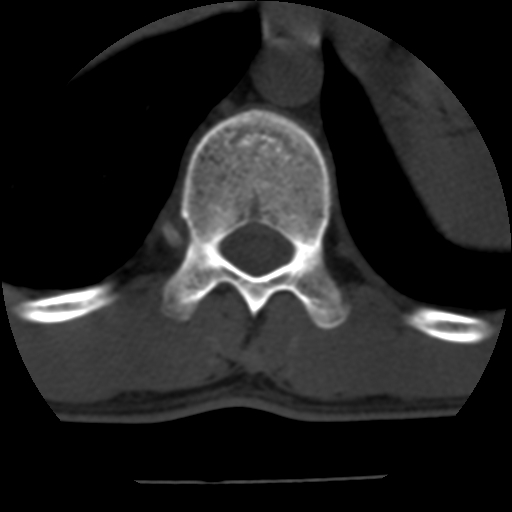

标题: CT10387:男,31岁,胸腰段CT [打印本页]

男,31岁,从6米高处坠落伤两天,腰背部疼痛,临床要求ct扫描胸10-腰1。请大家帮忙看看骨质有问题吗?

t12、l1锥体前缘轻度楔形变,平扫示椎体前缘骨小梁欠规整,第9幅图示椎体前缘骨质不连续,结合外伤史考虑椎体轻度压缩骨折。

楼主扫描层厚可能较大,每个椎体只有三个层面.

从所示层面分析,无明确骨折征象,象类似病人我个人会建议mri除外骨挫伤.

从上查骨窗第九片椎体前缘皮质显示断裂.压缩骨折?